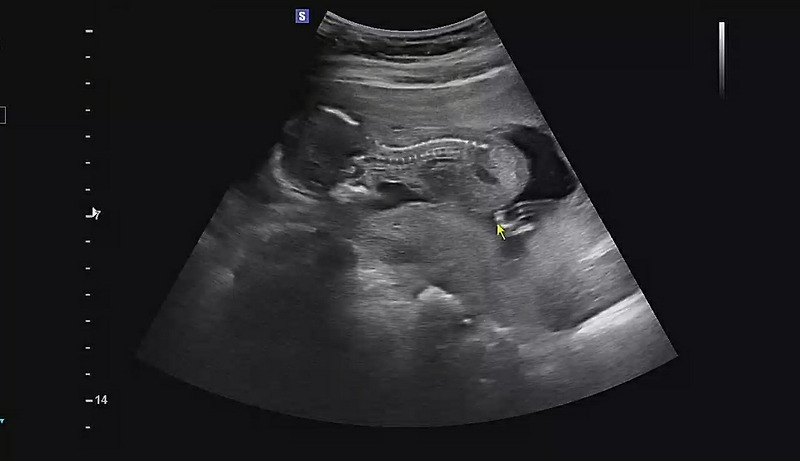

12주차 임신중독증검사로 베이비 아스피린 처방/16주차/17주차/18주차

안녕하세요 12주차에 높은 혈압으로 인해 산부인과에서 임신중독증 검사를 받았습니다 검사한지 1주일만에 결과가 나왔는데요 결과는 ... 임신중독증 고위험군으로 나왔습니다 ㅜㅜ 그래서 동